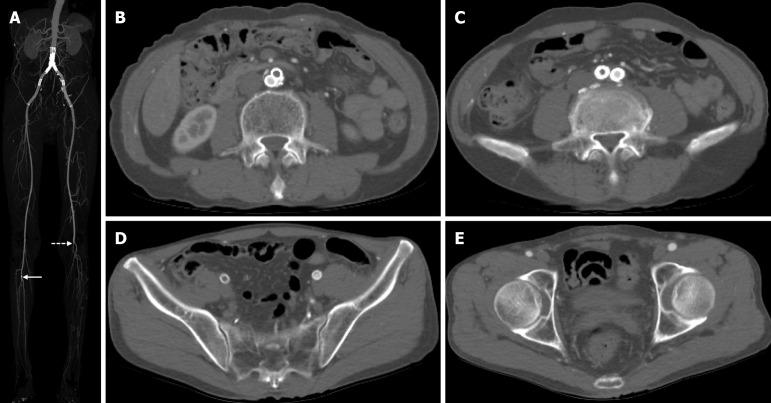

A 64-year-old male patient presented with severe claudication of the right leg. The patient's history included multiple prior interventions for aortoiliac lesions. The preoperative computed tomography (CT) imaging showed a thrombotic occlusion of right aortoiliac stenting. An Angiojet Omni thrombectomy catheter (Boston Scientific, Marlborough, MA, United States) was used to remove the thrombus in a retrograde fashion after the successful placement of the large-diameter sheath in the right common femoral artery for prevention of distal embolization. The remnant organized thrombus was removed with an over-the-wire Fogarty catheter (Edwards Lifesciences, Irvine, CA, United States). Completion angiogram and postoperative CT imaging demonstrated complete removal of thrombus and no evidence of distal embolization.

一名64岁男性患者出现严重的右腿间歇性跛行。该患者既往有多次主髂病变的介入治疗史。术前计算机断层扫描(CT)成像显示右主髂动脉支架血栓形成闭塞。在成功将大直径鞘管置入右股总动脉以预防远端栓塞后,使用Angiojet Omni血栓切除术导管(美国波士顿科学公司,马尔伯勒,马萨诸塞州)逆行清除血栓。用金属丝引导的Fogarty导管(美国爱德华生命科学公司,尔湾,加利福尼亚州)清除残余的机化血栓。血管造影完成和术后CT成像显示血栓已完全清除,无远端栓塞迹象。